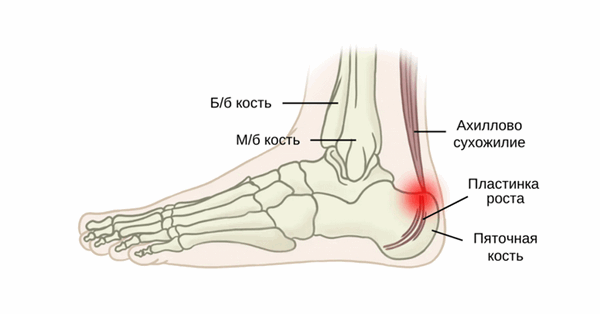

Апофиз имеет более высокий состав волокнистого хряща. Апофиз пяточной кости обычно появляется у детей в возрасте 7-9 лет и окостеневает как самостоятельный центр окостенения примерно к 15-17 годам. Ахиллово сухожилие вставляется в нижнюю, заднюю и слегка медиальную часть пяточной кости. Пластины роста пяточной кости подвергаются сильному напряжению со стороны подошвенного апоневроза и Ахиллова сухожилия [1].

Клинически значимая анатомия

Пяточная кость расположена в задней, подошвенной области стопы. Ахиллово сухожилие прикрепляется внизу, сзади и примерно посередине пяточной кости. Плантарная фасция берет начало от медиального бугорка в подошвенной части пяточной кости. Ближе к эпифизу лежит апофиз, куда ахиллово сухожилие фактически и вплетается. Ростковая зона пяточной кости и ее апофиз испытывают большую нагрузку от плантарной фасции и ахилла. Кроме того, разница в темпе роста мышцы и кости может приводить к укорочению трицепса голени, в результате чего может снизиться амортизация между стопой и поверхностью опоры. Кроме того, у ахиллова сухожилия имеется довольно широкая область прикрепления, которая анатомически связана с плантарным апоневрозом. Фактически это помогает предотвратить травматические разрывы центра оссификации.